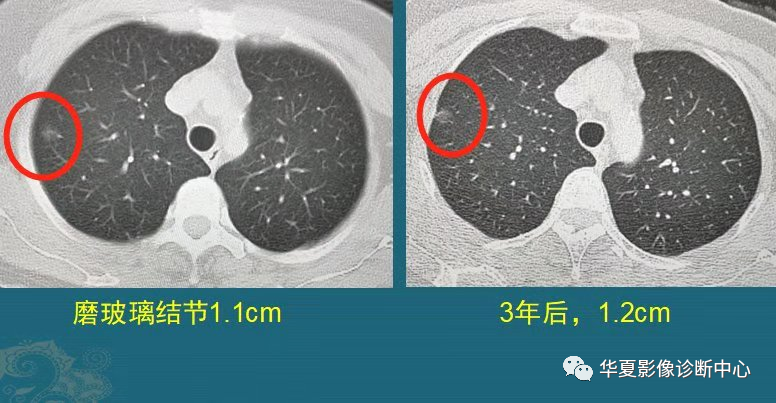

图5

这是一位中年女士,体检发现右肺纯磨玻璃结节1.1cm,定期复查,3年后好像增大了一点,直径大约1.2cm,边缘出现少量细索条影,她不想再观察了,做了胸腔镜微创手术,病理是原位腺癌。